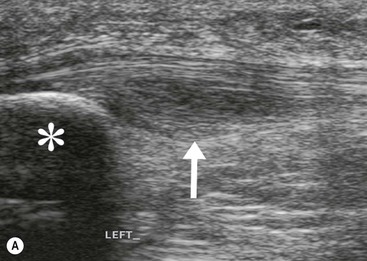

The affected tendon is thickened and hyporeflective on US, with neovascularisation on Doppler imaging (Fig. 46-16). High SI is demonstrated on fluid-sensitive MRI sequences (Fig. 46-17). Tendon tears are demonstrated as focal areas of deficiency.13 In chronic cases, new bone formation may be seen on radiographs at the tendon enthesis. Calcific tendinopathy is much less common than in the rotator cuff of the shoulder.